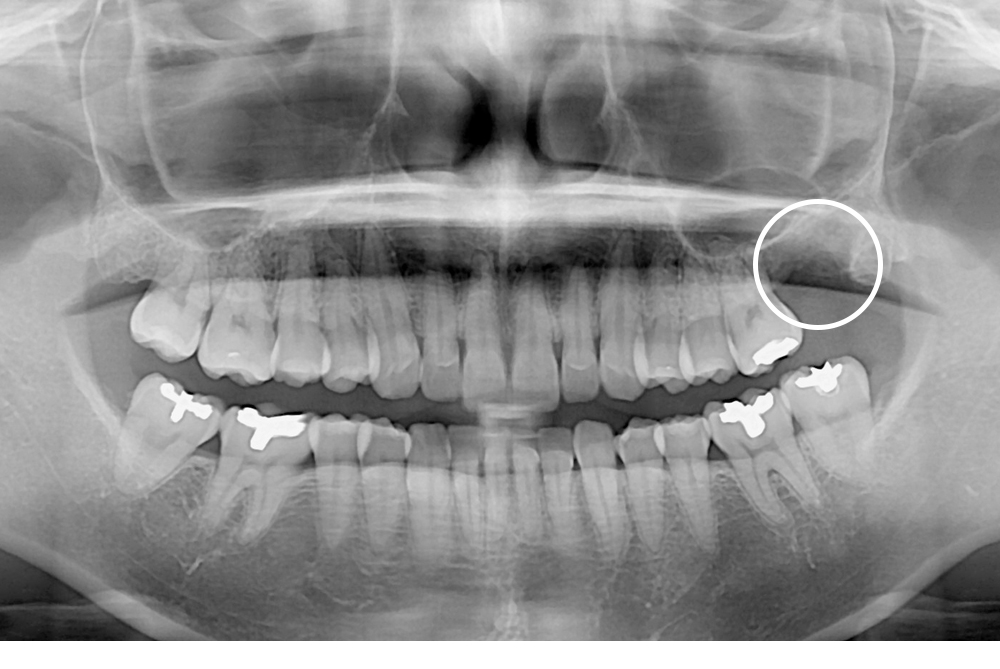

[사랑니] 매복 사랑니 발치

치료후 : 2020-01-22

세종치과는 구강악안면외과학 박사이신 원장님이 발치하는 치과입니다.